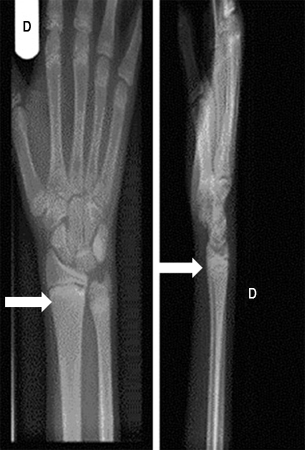

Punho direito de um paciente com raquitismo por deficiência de vitamina D depois do tratamento (setas)

Seerat I, Greenberg M. Hypocalcaemic fit in an adolescent boy with undiagnosed rickets. BMJ Case Reports 2010; doi:10.1136/bcr.10.1136/bcr10.2008.1153